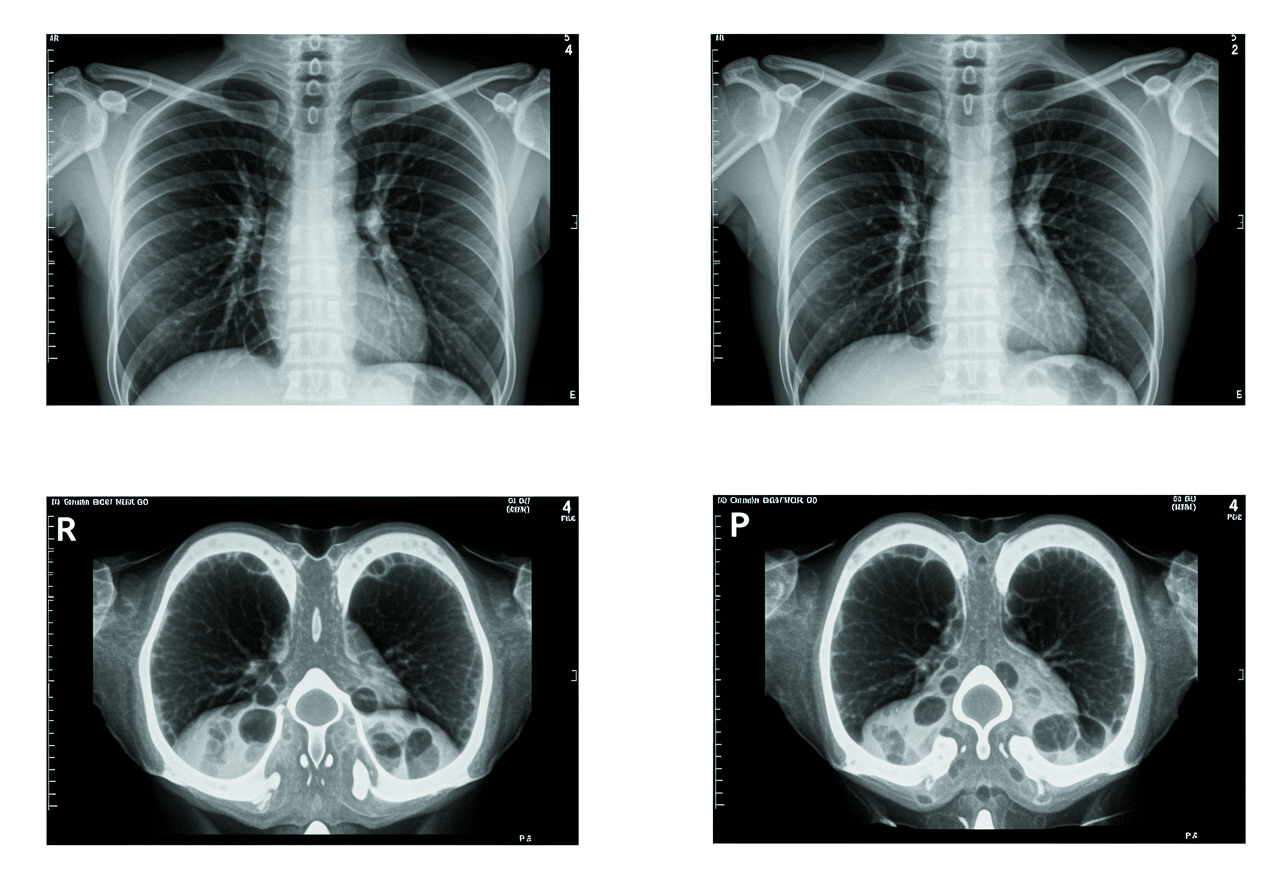

Emergency physician reviewing chest X-ray and CT angiogram at Priority ER

Board-certified emergency physicians providing immediate chest imaging interpretation and treatment